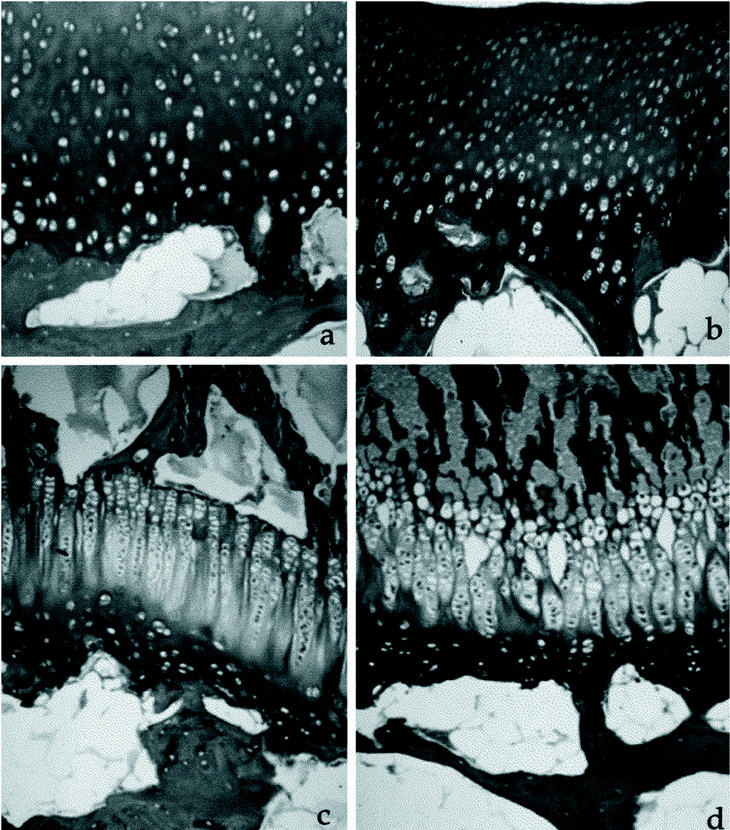

En las tibias sometidas a elongación no se observaron alteraciones morfológicas importantes comparando con las tibias no elongadas (Fig. 2).

Figura 2. Cartílago articular a) control, b) elongado (3 mm/día) (Tricrómico de Masson, ×100). Cartílago de crecimiento, a) control, b) elongado (3 mm/día) (Tricrómico de Masson, ×100)

En el cartílago articular (tabla 1) no se encontraron diferencias en el área de matriz extracelular. Se vio un aumento del área celular en las capas media (p < 0,01) y profunda (p < 0,05) de las tibias elongadas a 1 mm/día y en la capa media de las tibias elongadas a 3 mm/día (p < 0,01).

La altura del cartílago articular no mostró diferencias en los diferentes grupos, ni en la longitud total, ni en las capas superficial ni media. Únicamente, en la capa profunda se observó un aumento en los grupos elongados a 2 mm/día (p < 0,01) y 3 mm/día (p < 0,05) y una disminución en el grupo elongado a 1 mm/día (p < 0,05). La altura epifisaria total no presentó diferencias en ninguno de los grupos analizados.

En el cartílago de crecimiento (tabla 2), la altura fisaria total mostró una disminución en el grupo elongado a 1 mm/día (p < 0,05) y en el grupo elongado a 3 mm/día (p < 0,001). Midiendo individualmente las capas, se demostró que la capa germinativa perdió altura en el grupo elongado a 2 mm/día (p < 0,05). Por su parte, la capa proliferativa disminuyó en el grupo elongado a 1 mm/día (p < 0,05) y en el elongado a 3 mm/día (p < 0,001). También se encontró un aumento de la altura en la capa hipertrófica del grupo elongado a 1 mm/día (p < 0,001).

Como ocurre con la altura, también el área total disminuyó significativamente (p < 0,01) en los grupos I y III. Analizando el área por capas, observamos que las capas germinativa y proliferativa disminuyen en el grupo I (p < 0,01) y en el grupo II (p < 0,05). Por su parte, la capa hipertrófica aumenta su área en los grupos I y III (p < 0,05).

El área de hueso trabecular (tabla 3) disminuyó, de forma altamente significativa, en todas las zonas estudiadas de los especímenes elongados a 1 mm/día (p < 0,001). En el grupo II encontramos diferencias estadísticamente significativas en el área de hueso metafisario (p < 0,001), de hueso pre-fisario (p < 0,001) y post-fisario (p < 0,05). En el grupo III, las diferencias fueron en el área de hueso subcondral (p < 0,01), epifisario (p < 0,001), pre-fisario (p < 0,001) y metafisario (p < 0,05).